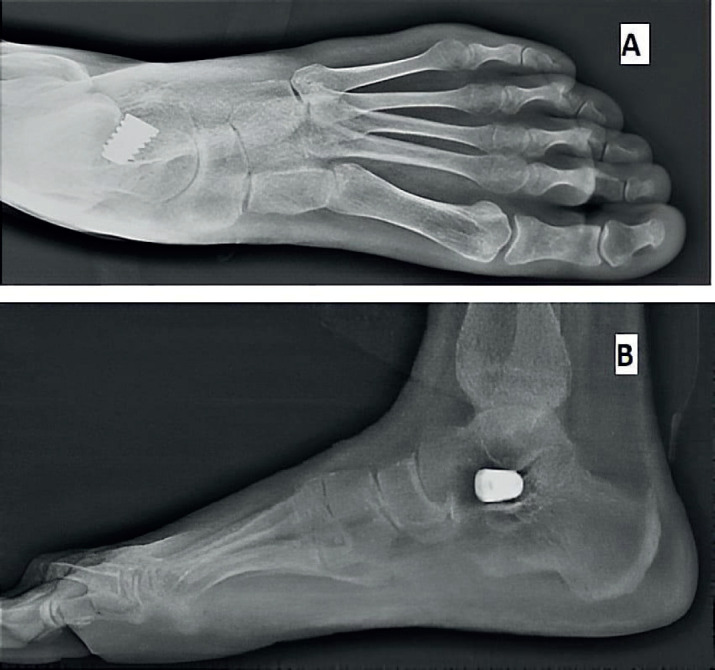

Methods: This is a prospective study and included 26 feet in 19 patients who underwent subtalar arthroereisis for symptomatic flexible flatfeet deformity. Preoperative and postoperative functional assessment based on the American Orthopedic Foot and Ankle Society (AOFAS) hindfoot scale. Radiographic parameters included preoperative and postoperative Kite`s angle, talonavicular coverage angle, Anterior-Posterior talo-1st metatarsal angle, Meary`s angle, talar declination angle, calcaneal inclination angle and lateral talocalcaneal angle.

Results: The mean follow-up period was 22.5±9.4 months and the mean preoperative AOFAS score was 54.6±6.0, while the mean AOFAS score at the last follow-up visit was 86.3±3.9 (P<0.001).The mean preoperative and postoperative radiological measurements were 19.0°±8.2° and 7.4°±3.9° for the AP Talo-1st metatarsal angle (P<0.001); 23.6°±9.1° and 8.0°±4.0° for talonavicular coverage angle (P<0.001); 35.4°±3.7° and 24.1°±3.4° for Kite`s angle (P<0.003); 22.4°±6.1° and 7.5°±3.7° for Meary`s angle (P<0.001); 41.0°±4.4° and 25.2°±7.1° for talar declination angle (P<0.001); 13.5°±3.7° and 21.3°±3.6° for calcaneal inclination angle (P<0.001) and 52.4°±7.2° and 42.9°±4.8° for lateral talocalcaneal angle (P<0.041) respectively.

Conclusion: Subtalar arthroereisis is an effective and minimally invasive procedure that showed clinical and radiological improvement for symptomatic flexible flatfoot in our study group.